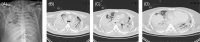

COVID-19 has affected over a billion people around the world, with over 2 million losing their lives (Worldometer). About 10% of patients infected with COVID-19 develop a serious illness, including respiratory failure, that require advanced life-supporting measures. Mortality among this subgroup exceeds 60%. We present a case of an otherwise healthy 34-year-old male who developed end-stage pulmonary fibrosis following COVID-19 infection. He achieved haemodynamic stability with mechanical ventilation and extracorporeal membrane oxygenation (ECMO) but did not show any sign of weaning off ECMO; however, he successfully underwent bilateral lung transplantation.